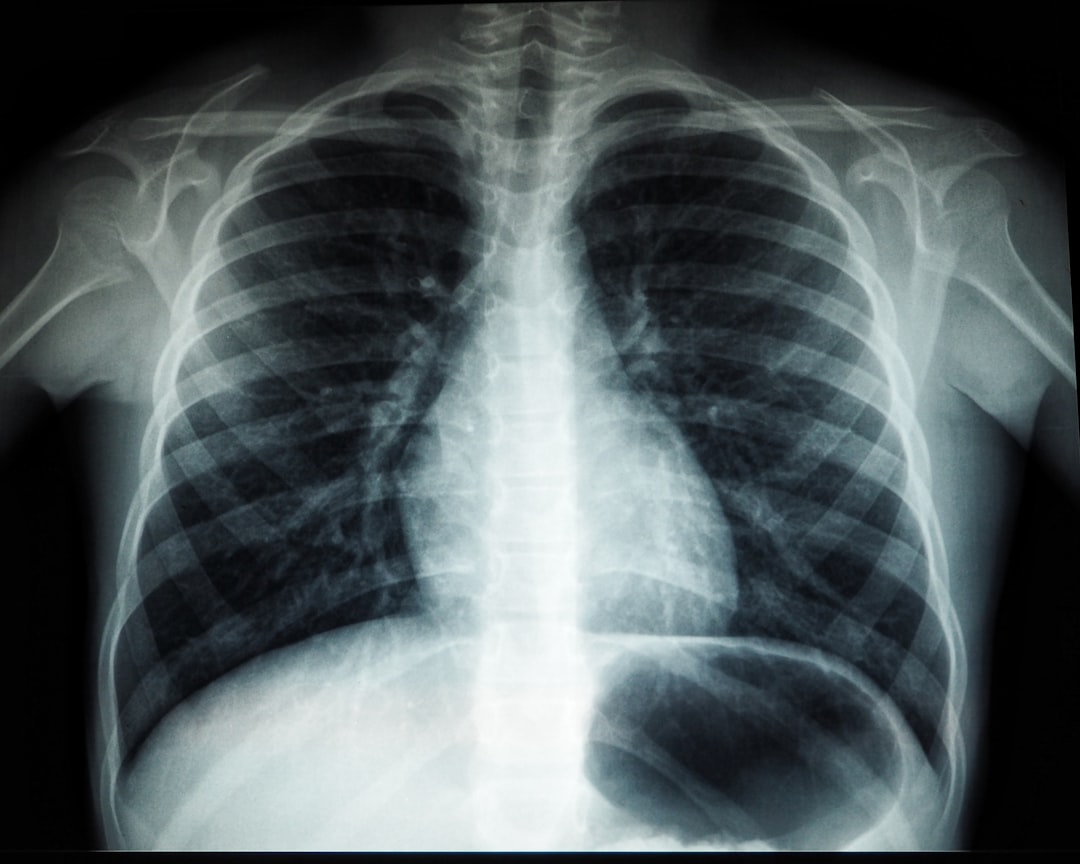

마지막으로, X-ray 등을 통한 영상 검사가 필요한 경우도 있습니다. 환자의 증상이나 검사 결과에 따라 다르게 결정할 수 있습니다. 결핵 검사 방법이 다양하니, 자신의 상황에 맞는 방법을 선택하여 진행하는 것이 바람직합니다. 결핵 검사 방식에 대한 이해가 깊을수록 더욱 적극적으로 자신의 건강을 지킬 수 있게 됩니다.